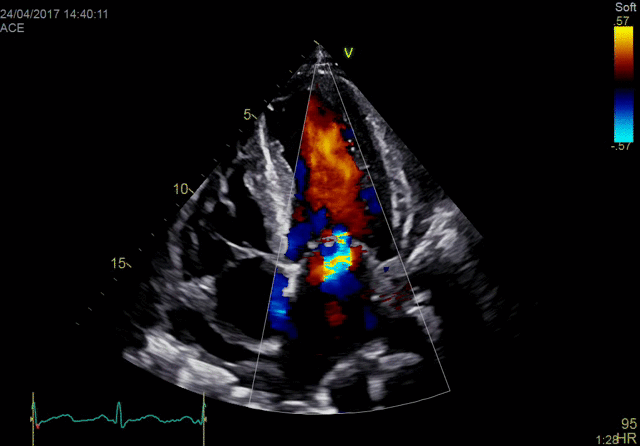

Vivid E95